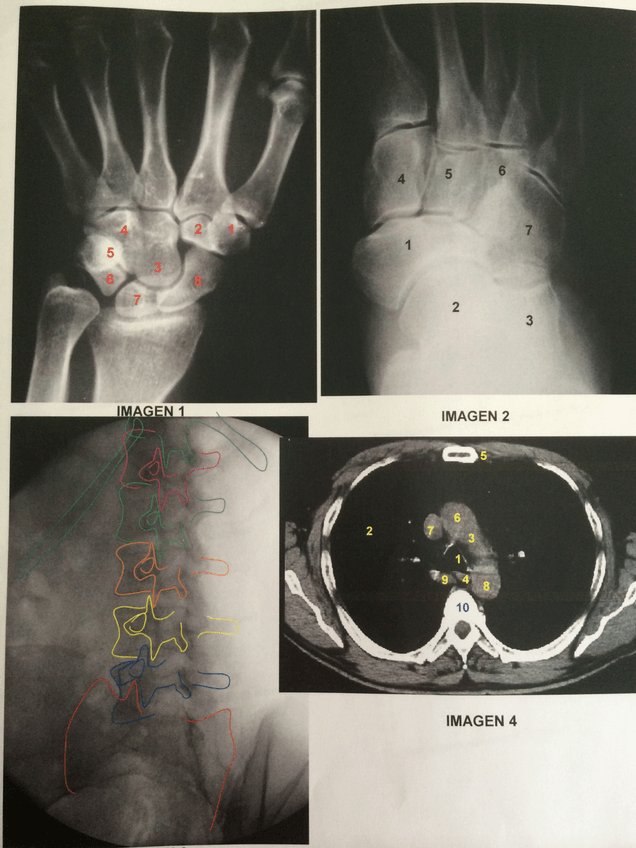

PRACTICA-3-TECNICA-ANATOMIA-MS.pdf

Practica-4-Tecnica-Anatomia-MI.pdf

Practica-5-Columna-Vertebra-Anatomia-patologica.pdf